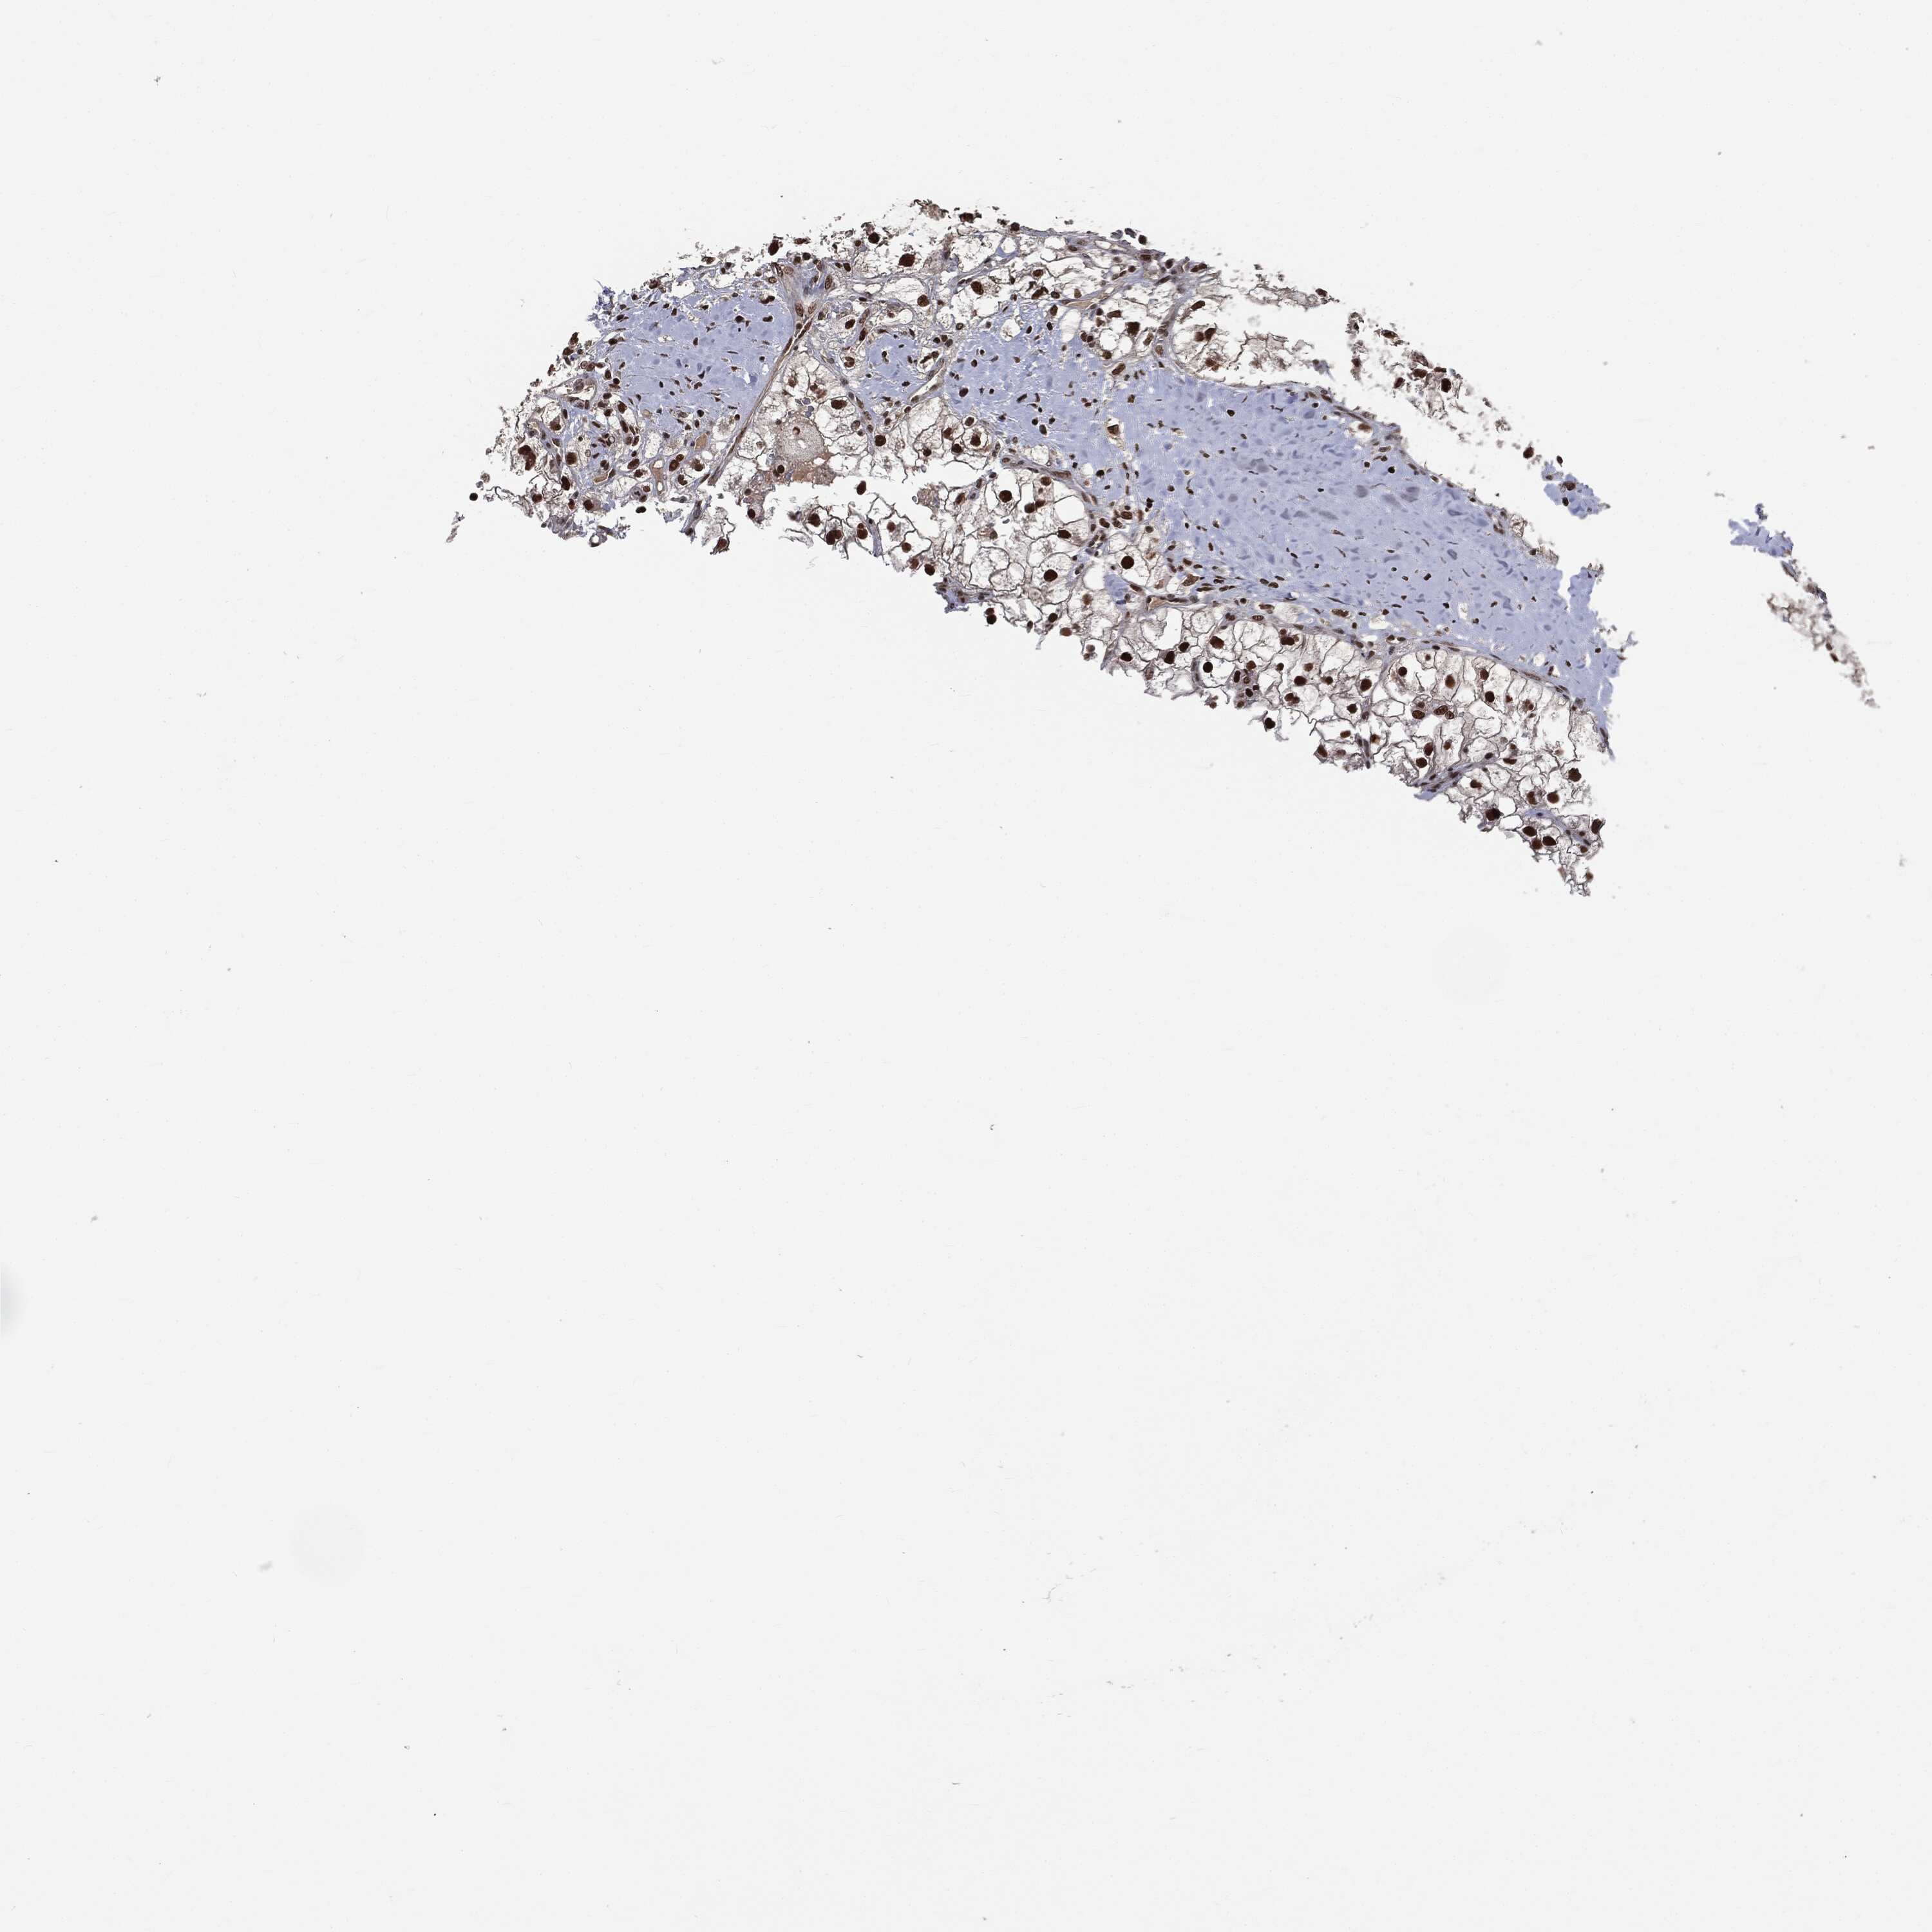

KIDNEY RENAL CLEAR CELL CARCINOMA (VALIDATION) - Interactive survival scatter ploti

The Survival Scatter plot shows the clinical status (i.e. dead or alive) for all individuals in the patient cohort, based on the same data that underlies the corresponding Kaplan-Meier plots. Patients that are alive at last time for follow-up are shown in blue and patients who have died during the study are shown in red.

The x-axis shows the expression levels (FPKM) of the investigated gene in the tumor tissue at the time of diagnosis. The y-axis shows the follow-up time after diagnosis (years). Both axes are complimented with kernel density curves demonstrating the data density over the axes. The top density plot shows the expression levels (FPKM) distribution among dead (red) and alive patients (blue). The right density plot shows the data density of the survived years of dead patients with high and low expression levels respectively, stratified using the cutoff indicated by the vertical dashed line through the Survival Scatter plot. This cutoff is automatically defined based on the FPKM cutoff that minimizes the p-score. The cutoff can be changed by dragging the vertical line or by entering a cutoff value in the square labeled "Current cut-off".

Under the Survival Scatter plot the p-score landscape (black curve; left axis) is shown together with dead median separation (red curve; right axis). Dead median separation is the difference in median mRNA expression between patients who have died with high and low expression, respectively. It is calculated as follows: median FPKM expression of dead patients with high expression - median FPKM expression of dead patients with low expression. This is intended to aid the user in visually exploring custom cutoffs and the associated p-scores and dead median separation.

Individual patient data is displayed and can be filtered by clicking on one or more of the category buttons on the top of the page. Categories describing expression level and patient information include: high, low, alive, dead, female, male and tumor stages. The scale of the x-axis can be toggled between linear and log-scale by clicking on the "x log" button. Mouse-over function shows TCGA ID, patient information and mRNA expression (FPKM) for each patient.

& Survival analysisi

Kaplan-Meier plots summarize results from analysis of correlation between mRNA expression level and patient survival. Patients were divided based on level of expression into one of the two groups "low" (under cut off) or "high" (over cut off). X-axis shows time for survival (years) and y-axis shows the probability of survival, where 1.0 corresponds to 100 percent.

DPH2 is not prognostic in Kidney Renal Clear Cell Carcinoma (validation)

Best expression cut offi

Based on the FPKM value of each gene, patients were classified into two groups and association between prognosis (survival) and gene expression (FPKM) was examined. The best expression cut-off refers the FPKM value that yields maximal difference with regard to survival between the two groups at the lowest log-rank P-value. Best expression cut-off was selected based on survival analysis .

When clicking on this number, the vertical dashed line indicating cut-off, the interactive survival plot, and the Kaplan-Meier curve will be adjusted to show results based on the best expression cut-off.

: 10.68

Median expressioni

Median expression refers to the median FPKM value calculated based on the gene expression (FPKM) data from all patients in this dataset. When clicking on this number, the vertical dashed line indicating cut-off, the interactive survival plot, and the Kaplan-Meier curve will be adjusted to show results based on the median expression.

: N/A

Median follow up timei

Median follow up time refers to the median time (years) after diagnosis with this type of cancer, based on clinical data from all patients in this dataset.

P scorei

Log-rank P value for Kaplan-Meier plot showing results from analysis of correlation between mRNA expression level and patient survival.

N/A

5-year survival highi

5-year survival for patients with higher expression than the expression cutoff.

For melanoma and glioma, 3-year survival is shown.

5-year survival lowi

5-year survival for patients with lower expression than the expression cutoff.

TCGA RNA samplesi

RNA-seq data is reported as average FPKM (number Fragments Per Kilobase of exon per Million reads), generated by the The Cancer Genome Atlas (TCGA) .

Normal distribution across the dataset is visualized with box plots, shown as median and 25th and 75th percentiles. Points are displayed as outliers if they are above or below 1.5 times the interquartile range. FPKM values of the individual samples are presented next to the box plot.

Average pTPM 10.1

Number of samples 100